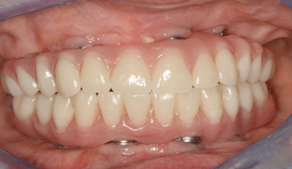

Fig 10. Recording a repeatable centric position was virtually impossible for this patient due to spasticity of the masticatory system. Among the compromises necessary in creating an occlusal scheme was to revert to a monoplane approach.

Figure 10

Fig 11. Recording a repeatable centric position was virtually impossible for this patient due to spasticity of the masticatory system. Among the compromises necessary in creating an occlusal scheme was to revert to a monoplane approach.

Figure 11

A patient with tardive dyskensia, for example, may experience dramatic changes in expressive facial activity and corresponding dysfunction in the muscle memory needed to repeat a centric position.19,20 Figure 8 and Figure 9 show an 82-year-old patient who had previously been treated for depression, had a failing dentition, and was diagnosed with tardive dyskensia. Extreme uncontrolled contortions of the facial musculature were evident in the patient when attempting to record a high smile line; removal of enough maxillary bone to hide the transition line was impossible. Dramatic compromises in occlusal scheme may be necessary to achieve even a moderately successful result; yet the implant approach realistically may be the only way to offer any functional improvement (Figure 10 and Figure 11).